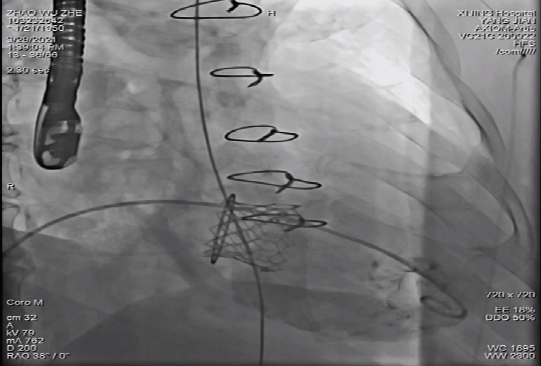

病例三

59岁女性,三尖瓣外科生物瓣置换术后,三尖瓣狭窄伴关闭不全,二尖瓣关闭不全,右心房明显增大,肺动脉高压,心功能Ⅳ级,三尖瓣瓣环面积521mm²,平均直径26.8mm。选用Prizvalve®29mm瓣膜进行植入,术后无瓣漏,无血管并发症。

该例患者由于右心房明显增大,导丝容易在心房内缠绕且无支撑力提供,瓣膜的推送跨瓣存在极高的难度。术中,杨剑教授、李飞教授和刘洋教授充分沟通,三人统筹规划分工操作,凭借三位术者各自高超的技艺和熟练的配合,在巨大右心房无任何支撑提供的条件下,顺利实现了输送系统的跨瓣和精准释放。

Prizvalve®瓣膜系统行三尖瓣瓣中瓣术后位置良好、造影无瓣漏